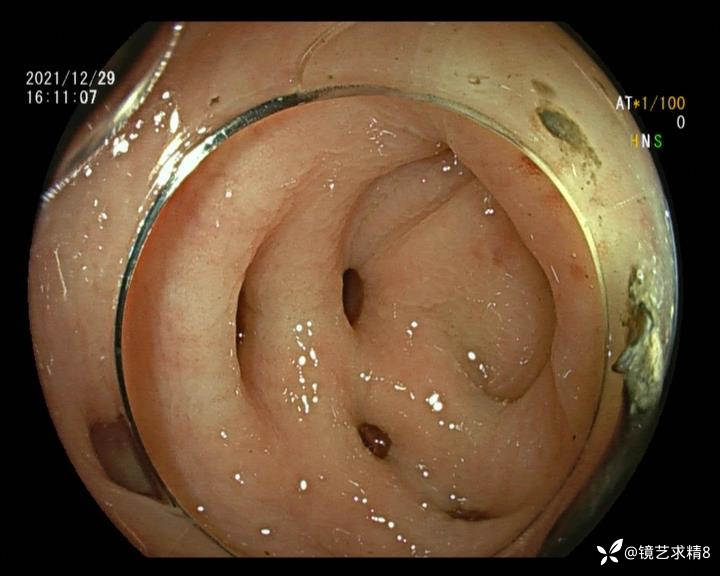

患者以消化道出血入院,胃镜未见异常,肠镜进入乙状结肠就看到很多憩室,同时还看到肠腔用清肠药后移动下来1枚尖锐的枣核,这么多憩室,这个枣核扎入憩室的机会非常大,推测应该是掉入一坑🕳就算出来还会有很多坑🕳🕳🕳等着,掉入憩室内很容易刺破血管,这可能就是消化道出血的原因,继续前进可以看到有一些憩室内翻,还有一些息肉,问题来了,那么多憩室,犯罪分子是抓住了,它在那些憩室内作过案?到达回盲部后挨个冲洗,但憩室大小又不足以把镜头进入憩室内观察,针对有血块的憩室冲洗后可疑出血的以夹子闭合或套扎,取出枣核,如果有锥形透明帽可能钻入憩室精准电凝效果更好,若内镜下操作失败介入治疗成功率更高,经内镜下治疗后观察未再出血出院。

亚洲人群结肠憩室主要发生在右半结肠,然后随着年龄的增长而延伸到左半结肠和双侧结肠。相比之下,欧美人群80%的结肠憩室好发于左半结肠,其中乙状结肠憩室占 70%,而大多是假性憩室。 然而,与憩室炎主要发生在左半结肠不同,东西方人群的憩室出血均主要发生在右半结肠,可能与右半结肠的憩室更宽大及憩室血管更易受到损伤相关。